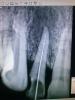

privetik Опубликовано 7 ноября, 2013 Поделиться Опубликовано 7 ноября, 2013 добрый день. каков прогноз у данного зуба??? надо ли его сохранять ??Протокол к,н-файлы 15-40, паркан, вода, хлоргексидин. из канала выделился гной. пломбировка септомексином. назначены антибиотики Ссылка на комментарий

privetik Опубликовано 7 ноября, 2013 Автор Поделиться Опубликовано 7 ноября, 2013 из анамнеза зуб раннее немного беспокоил. перкуссия безболезнена. боль в при пальпации в проекции апекса Ссылка на комментарий